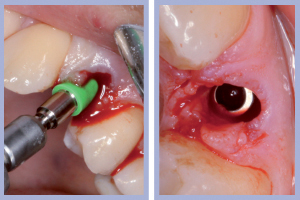

- Figg. 9a, b – Preparazione del sito di destra

- Figg. 10a, b – Preparazione del sito di sinistra

– Preparazione del sito implantare con tecnica flapless (Figg. 9-10);

Dopo l’estrazione, eseguita con i consueti passaggi di scollamento-lussazione-estrazione, la revisione chirurgica tramite cucchiaio alveolare consentiva la completa rimozione dei frustoli di tessuto di granulazione e di legamento parodontale residuo. La preparazione del sito implantare veniva effettuata con approccio flapless, ovvero senza l’esecuzione del lembo.

Una volta determinato, sul versante palatale dell’alveolo, il giusto asse di preparazione, si lavorava fino alla profondità programmata; la sequenza di frese comunemente impiegate per il diametro implantare da posizionare completava la preparazione dell’alveolo chirurgico. Non era richiesto l’uso della fresa svasatrice dal momento che a livello cervicale l’alveolo presentava un diametro maggiore di quello implantare.